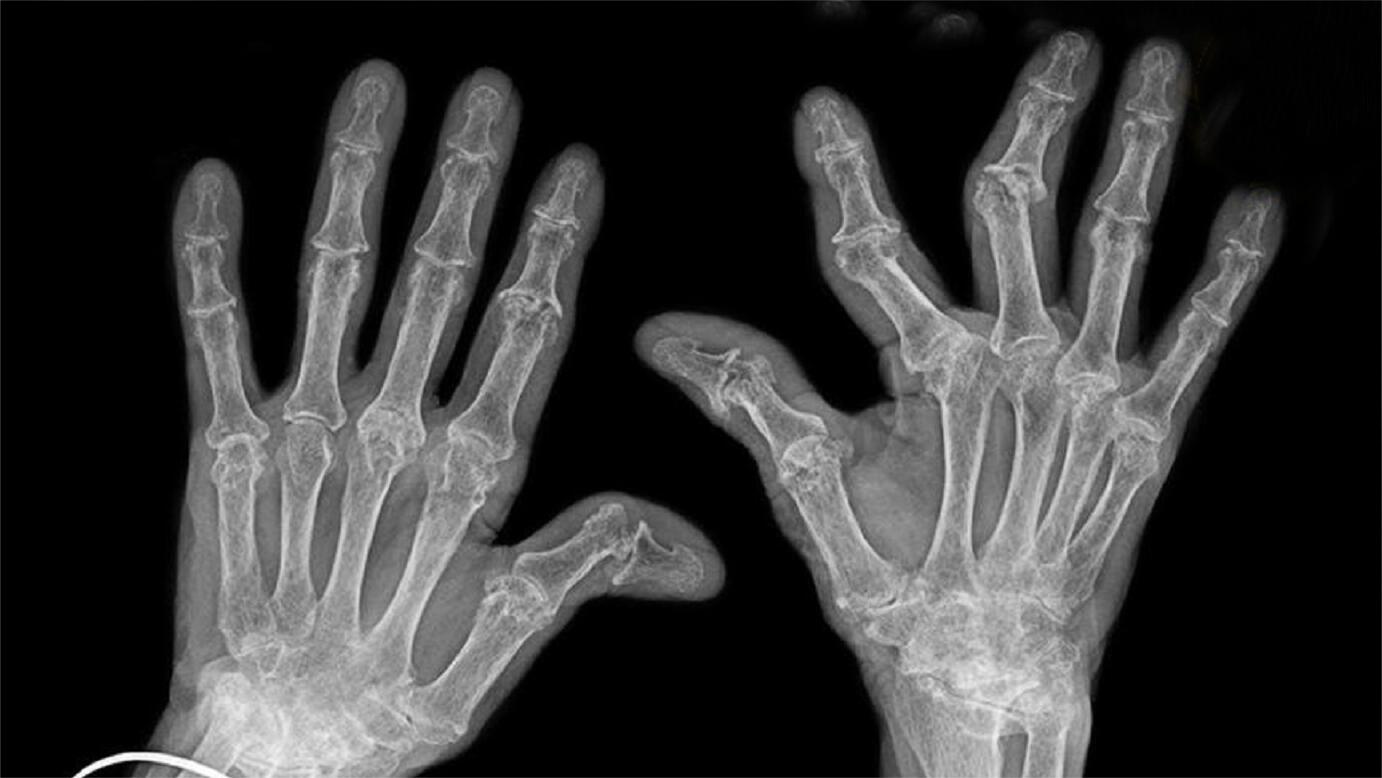

相关疾病: 痛风 患者:女,68岁,左手环指远节指骨破坏,病史不详

图片尺寸640x853

筋骨堂手指关节疼痛变形是骨关节炎还是类风湿

图片尺寸560x448